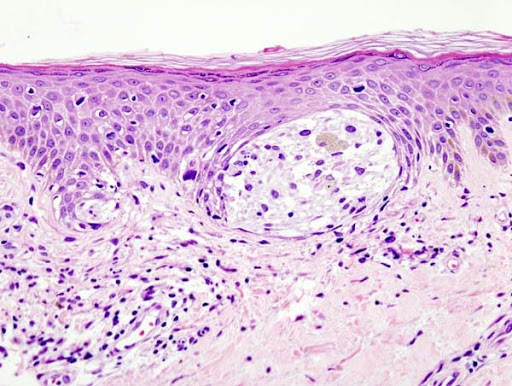

SKIN TISSUE EXAMPLES

Also, a lot of slides have something like this on it. Could you maybe help me figure out what it is?